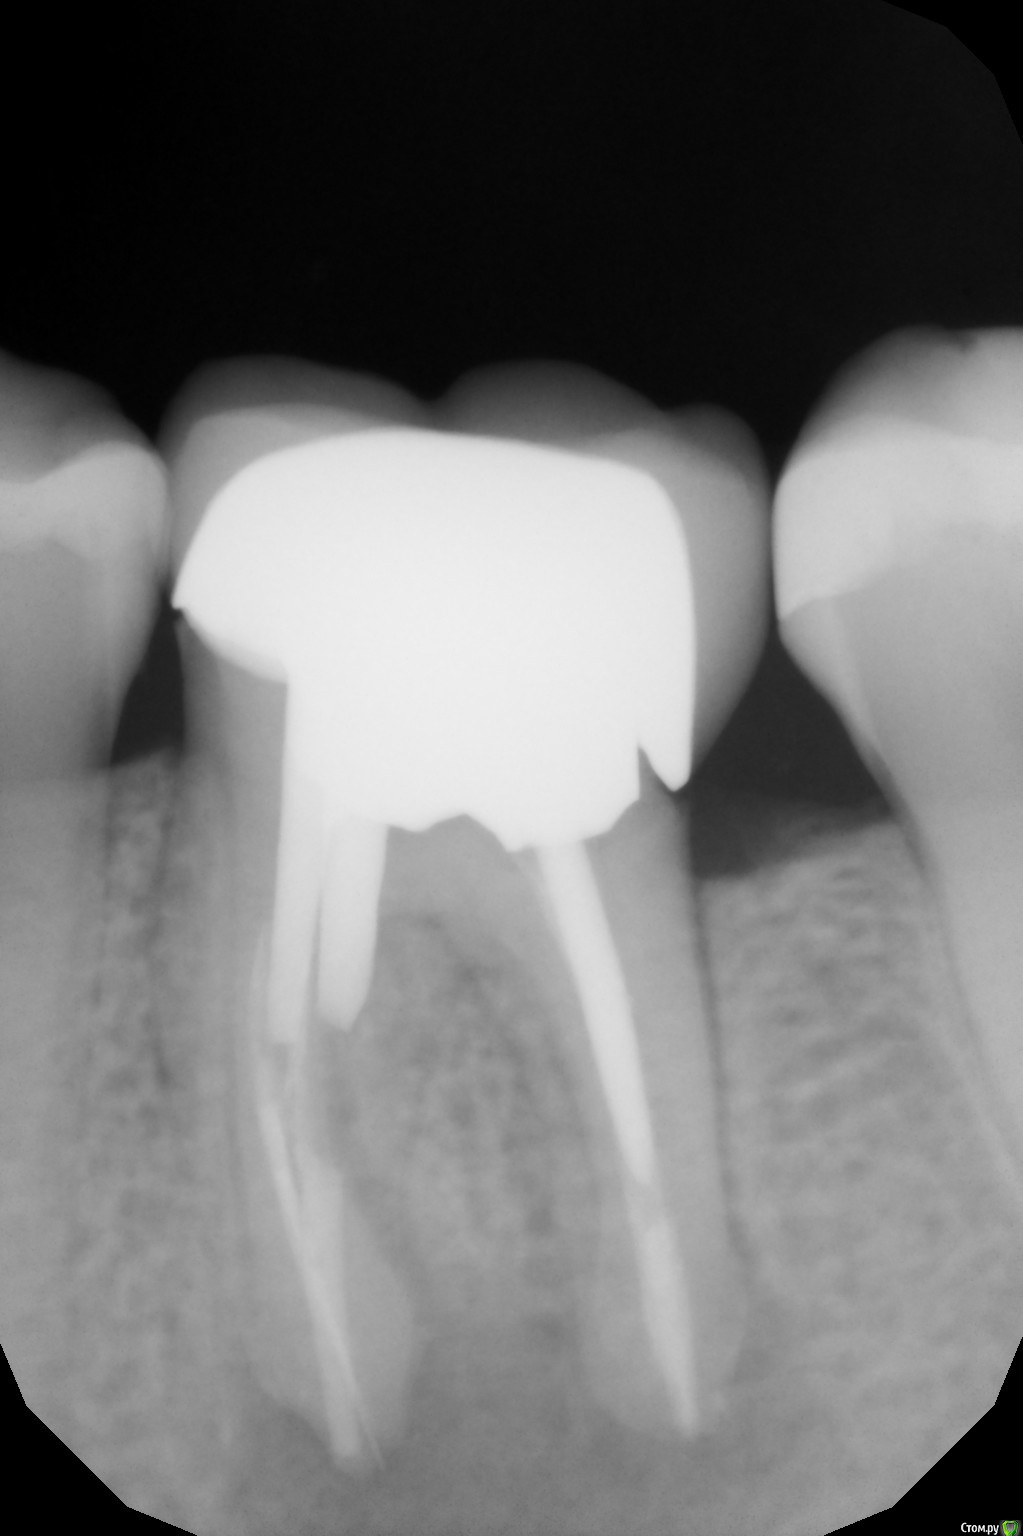

DenisB Опубликовано 15 февраля, 2020 Поделиться Опубликовано 15 февраля, 2020 Здравствуйте! Стал немного побаливать зуб под коронкой, особенно если жевать им твердую пищу (баранки и т.д.). Причем иногда ноющая боль есть, иногда - нет. Коронку на зуб ставили в 2013 году. Сходил к стоматологу, сделали рентген, обнаружили кисту под зубом (см. фото). Стоматолог говорит, что нужно удалять зуб, после этого ставить имплант. Вопрос: возможны ли какие-то другие варианты убрать эту кисту или в данном случае поможет только удаление? Ссылка на комментарий

dima3M Опубликовано 16 февраля, 2020 Поделиться Опубликовано 16 февраля, 2020 Наличие вкладки, большой зоны воспаления и фрагмента инструмента в канале резко снижают прогноз на выздоровление после повторного лечения.Целесообразнее удаление и потом имплантация Ссылка на комментарий